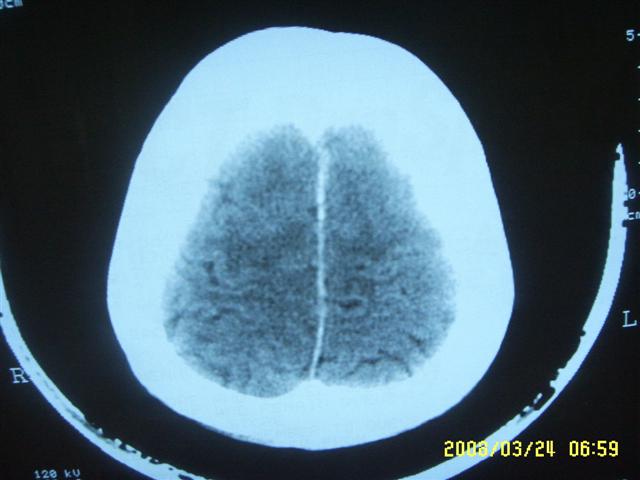

以下是引用dyqct在2008-4-2 20:09:00的发言:[br]考虑为:神经纤维瘤病(nf1型)。建议增强进一步检查。